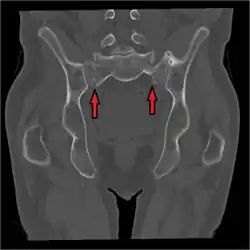

Sacral fracture

A sacral fracture is a break in the sacrum bone.[1] The sacrum is the large triangular bone that forms the last part of the vertebral column from the fusion of the five sacral vertebrae. Sacral fractures are relatively uncommon. They tend to be caused by high-energy trauma, for example in road traffic accidents or in falls.[2]